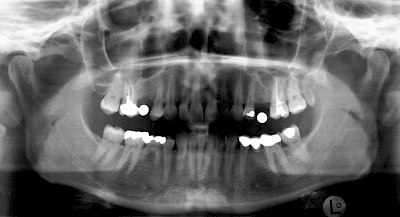

Knochenaufbau und Implantateinsatz

Ist nicht genügend Knochen zur Verankerung eines Implantates vorhanden, kann über einen sogenannten Knochenaufbau die Möglichkeit für das Einbringen eines Implantates geschaffen werden. Dazu kann z. B. Knochen aus der Kieferwinkelregion oder auch aus der Kinnregion entnommen und im Bereich der Fehlstellen aufgetragen werden. Auch künstliches Knochenmaterial kann dabei zum Einsatz kommen.

Im Oberkiefer wird – wenn ein Knochenaufbau notwendig ist – der Knochen in der Regel nicht außen "aufgelegt", sondern es wird der Boden der Kieferhöhle entweder über den Implantat-Bohrkanal durch Verdichtung nach oben gedrückt (interner Sinuslift) oder über eine Fensterung der vorderen knöchernen Kieferhöhlenwand kann Knochen im Bereich des Kieferhöhlenbodens eingebracht (externer Sinuslift).

Knochenaufbau im Unter- und Oberkiefer